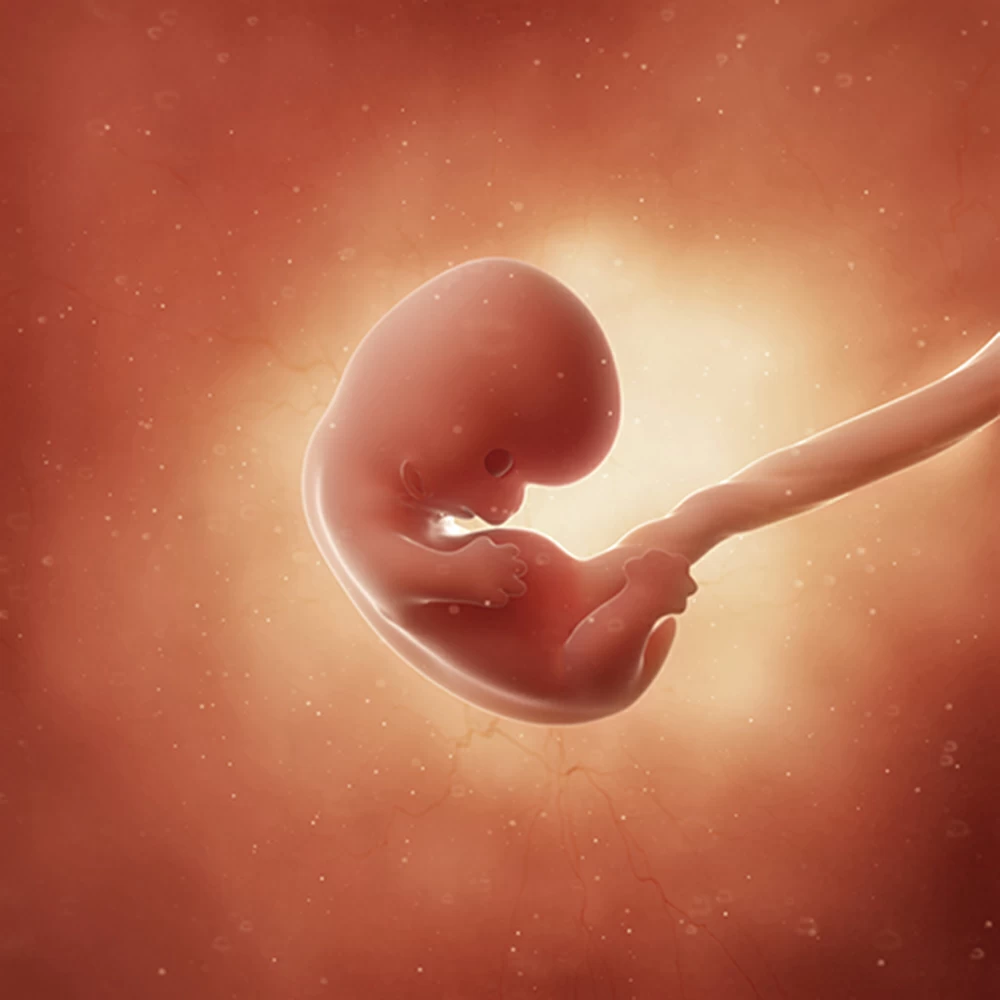

Беременность начинается с момента оплодотворения — слияния зрелой мужской клетки (сперматозоида) и женской яйцеклетки. В результате деления получается многоклеточный организм, который похож на ягоду ежевики (на латыни «морус»), отчего зародыш на этом этапе называют морулой. Приблизительно на 7 сутки происходит внедрение морулы в стенку матки (имплантация). Ворсинки внешних клеток зародыша соединяются с кровеносными сосудами матки, впоследствии из них образуется плацента.

Наружные клетки морулы плотно врастают в слизистую оболочку матки. У зародыша начинается формирование пуповины, плаценты, а также нервной трубки, из которой впоследствии развивается нервная система плода.

Третья неделя беременности является сложным и важным периодом. В это время начинают закладываться важные органы и системы плода: появляются зачатки дыхательной, пищеварительной, кровеносной, нервной и выделительной систем. На месте, где вскоре появится головка плода, формируется широкая пластинка, которая даст начало головному мозгу. На 21 день у ребенка начинает биться сердце.

На четвертой неделе продолжается закладка органов плода. Уже присутствуют зачатки кишечника, печени, почек и легких,появляются складки туловища, и зачаток позвоночника (хорда).

К концу недели (примерно 27-28 дни) формируются мышечная система, позвоночник, который разделяет эмбрион на две симметричные половины, и верхние и нижние конечности. Начинается формирование ямок на головке, которые впоследствии станут глазами плода.